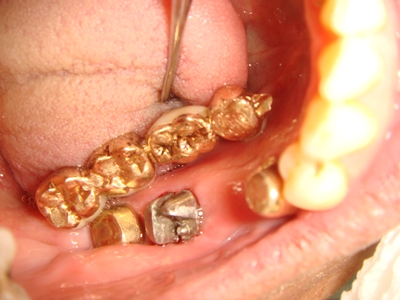

(上圖AA為牙根斷裂面)

New Taiwan Konus活套冠牙橋︰

1、可順利的拿下假牙 作清洗 治療

2、下圖(RR) Rest Arm (支靠臂) 用以分擔衰敗的第二小臼齒(AA)的承受力。免於斷、裂。

3、此案例CC大臼齒因無牙根分叉 腐坑 死穴的病灶 所以不必做牙根分切治療,作德國原型Konus內外冠即可。

4、BB有鑄球膠帽扣 穩住牙橋

* * * * * * * *